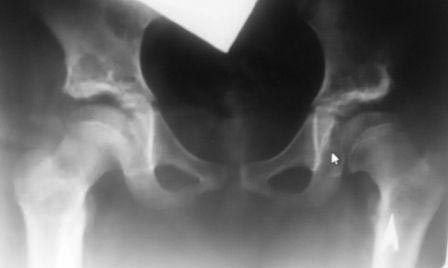

У нас реконструкция крыши делается по типу создание навеса (методика

УзНИИТО) в зависимости от недоразвития части крыши, ну чаще

передневерхней, сначала открываем сустав, ревизия, удаление

внутрисуставных тел, проверка хрящевой  губы, определение размера

недопокрытия головки,  дугообразная остеотомия крыши  по краю

прикрепления капсулы сустава к кости, параллельно стенки вертлужной

впадины до внутреннего кортикала , формируем крышу, после  устранение

торсии, вальгуса шейки и определяется размер укорочения, взятый

трансплантат внедряется в паз над крышей, примерно так.. То, что попало

в руки сейчас, примеры операции у пациентки 13лет, и результат у 12 лет,

до снимков не нашел, если найду еще отправлю.